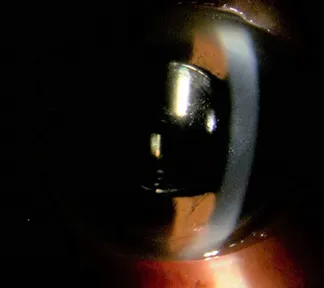

白内障とは

目の中のレンズである水晶体が濁って、見えにくくなることを白内障といいます。濁る原因の多くは加齢によるもので、誰にでもいつかは起こります。その他に、糖尿病や薬の影響で白内障になることもあります。ふつう濁りは急に進行することはありませんが、一度濁ってしまった水晶体は残念ながら元には戻りません。症状の軽いうちは、生活にそれほど問題はありませんが、ものが見えにくくなり、生活にも不自由を感じるようになれば、手術をする必要があります。